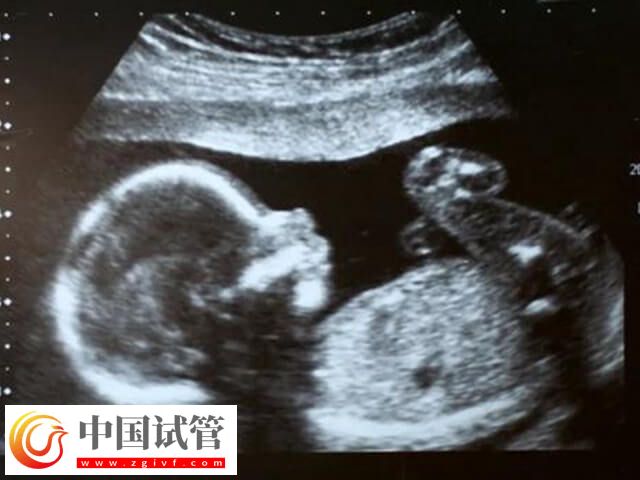

即第二次超声波检测,这个检查通常在怀孕8-10周的时间进行,这次检查主要是确认胎心的存在,检查胎儿发育是否正常,以及排除早期胎停育的可能性,如果检查正常的话,可继续妊娠,反之则需要在医生的指导下进行治疗。

试管婴儿三超即第三次超声波检测,这个检查通常在怀孕后的11-13周进行,这也算是常规的产前超声检查,主要用于检查胎儿是否存在畸形,如21三体综合征。如果NT值异常,可能需要进一步的产前诊断。